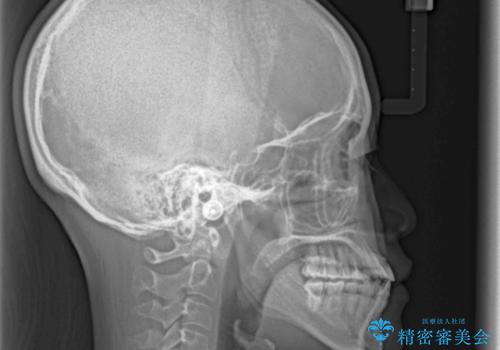

前歯のクロスバイトと変色した歯 ワイヤー矯正とセラミック治療

- 前歯のクロスバイトと神経を取り除いた後に変色してしまった前歯を気にして来院された患者様です。

ワイヤー矯正により矯正治療を行った後に、前歯の補綴治療を行うこととしました。

インビザラインでの矯正治療も十分に対応可能でしたが、自己管理の煩わしさから、ワイヤー矯正を行うこととしました。